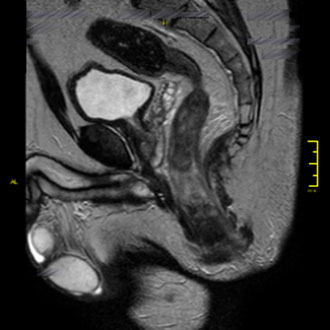

Bei Frauen liefert die MRT des Beckens wertvolle Informationen über die Harnblase, Gebärmutter, Eierstöcke und den Enddarm.

Die Untersuchung ermöglicht eine exakte Darstellung der Beckenorgane und hilft, gutartige von bösartigen Veränderungen zu unterscheiden – wichtig für eine gezielte Therapieplanung.